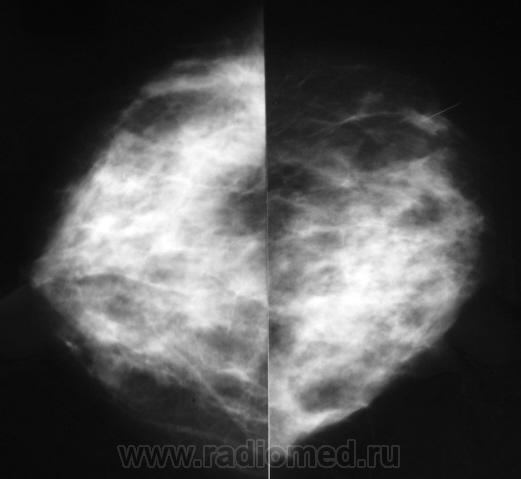

Пол пациента: Женский пол Тип патологии: Доброкачественное новообразование, киста Область исследования: Молочные железы Методы исследования: Rg Женщина обратилась в поликлинику по поводу дискомфорта в мол. железах. Сделали маммографию. https://radiomed.ru/sites/default/files/styles/case_slider_image/public/user/12/sl272959a_640x480.jpg?itok=bO4B39GN https://radiomed.ru/sites/default/files/styles/case_slider_image/public/user/12/sl272960_640x480.jpg?itok=TmZ56JLx https://radiomed.ru/sites/default/files/styles/case_slider_image/public/user/12/sl272960a_640x480.jpg?itok=b7Dedogx ID:5928 Чт, 26/08/2010 - 05:35 #1 mila Не на сайте Был на сайте: 5 лет 2 месяцев назад Зарегистрирован: 26.02.2010 - 02:56 Публикации: 277 Вы косые не делаете? Мастопатия, порекомендуйте УЗи учитывая выраженность железистого компонента и наличие единичных округлых теней не позволяющих исключить наличие кист (фиброаденом)

Вы косые не делаете? Мастопатия, порекомендуйте УЗи учитывая выраженность железистого компонента и наличие единичных округлых теней не позволяющих исключить наличие кист (фиброаденом)